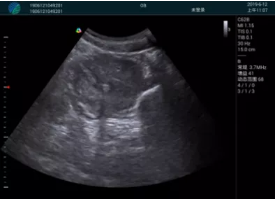

肝內血管顯示清晰,血流敏感無外溢

病例二:

甲狀腺囊性結節(jié),囊壁鈣化,透聲好

甲狀腺囊性占位